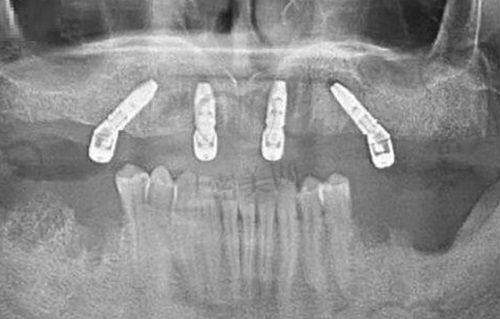

口腔全景机:可以拍摄口腔的全景图像,清晰显示牙齿、颌骨等结构的情况。医生通过全景机拍摄的图像,能够全方面了解患者的口腔状况,为制定治疗方案提供正确的依据。与传统的X光片相比,口腔全景机拍摄的图像更加全方面、清晰,减少了患者多次拍摄X光片的麻烦。

种植机:在牙齿种植过程中起着关键作用。精良的种植机具有高精度、稳定性好等特点,能够确保种植体正确植入到牙槽骨内,提高种植的成功几率。同时,种植机还配备了精良的操作系统,医生可以根据患者的具体情况调整种植参数,为患者提供个性化的种植治疗。